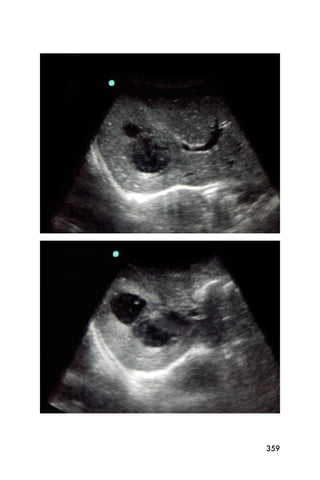

pregnant uterus has a thin hyperechoic white line in the

center that is the endometrium.

Figure 3. The bladder (*) and empty uterus (arrow)

An empty uterus may cause the clinician to worry about